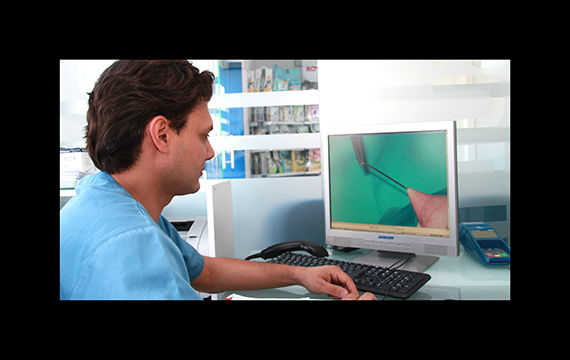

endoscopia

En clinican dispone de endoscopio para poder llegar a zonas que de otra forma no se puede llegar.